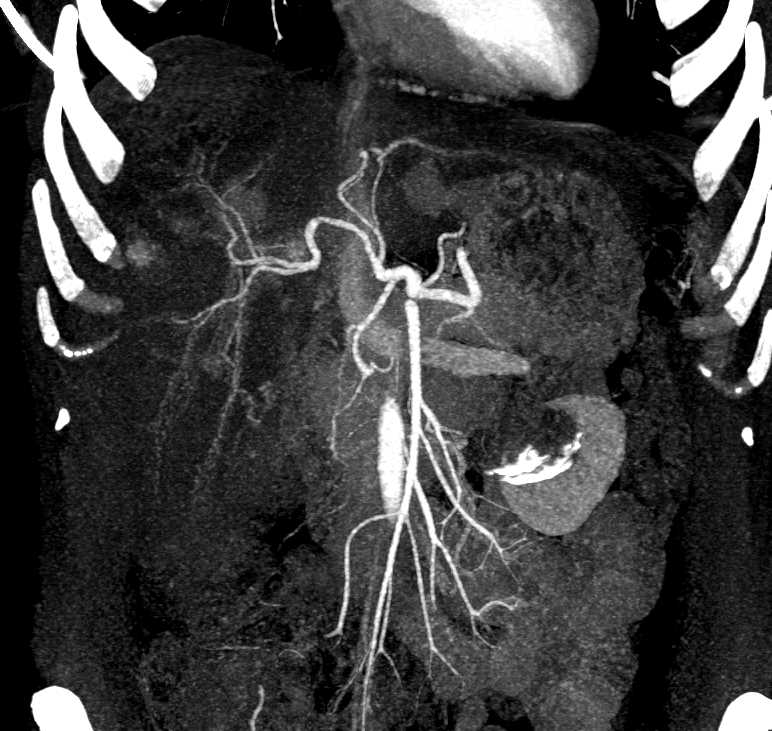

Biliary Cystadenoma Liver